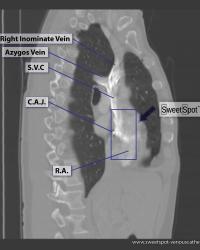

Cardiac anatomy conduction pathways |